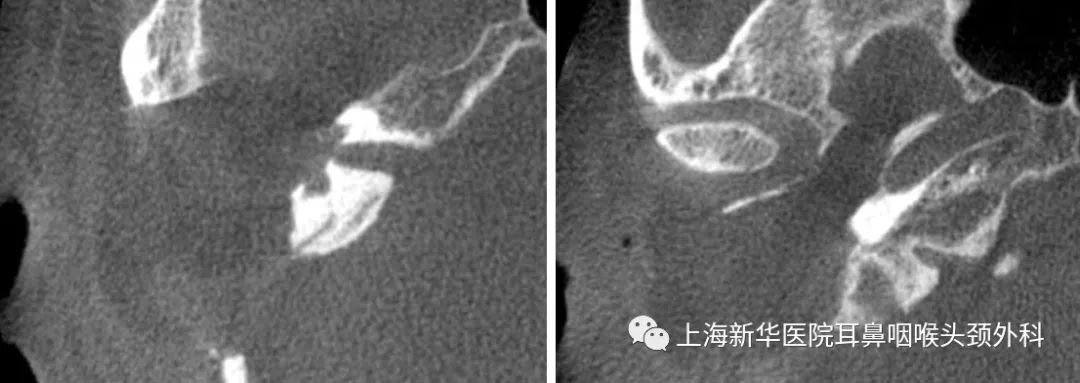

术后CT:

术后增强MRI: